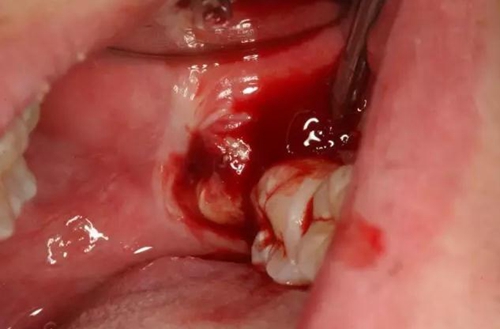

圖6.患者年輕、骨質比較軟。牙挺放置在38牙根近中,先用推力豎直38牙冠、然后用挺力直接挺出38

圖7.炎癥期拔牙出血較多、放置止血海綿一塊,壓迫止血半小時